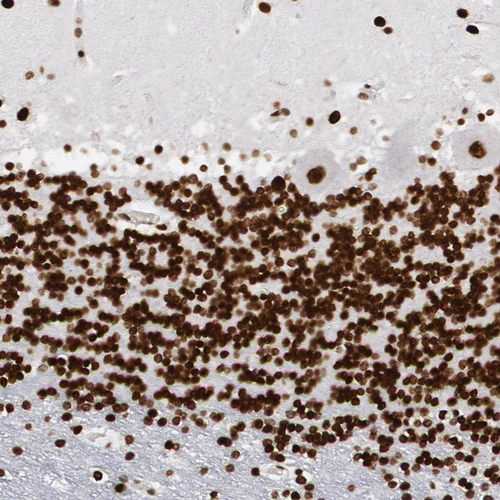

Immunohistochemical staining of human cerebellum, lymph node, prostate and testis using Anti-MECP2 antibody HPA001341 (A) shows similar protein distribution across tissues to independent antibody HPA000593 (B).